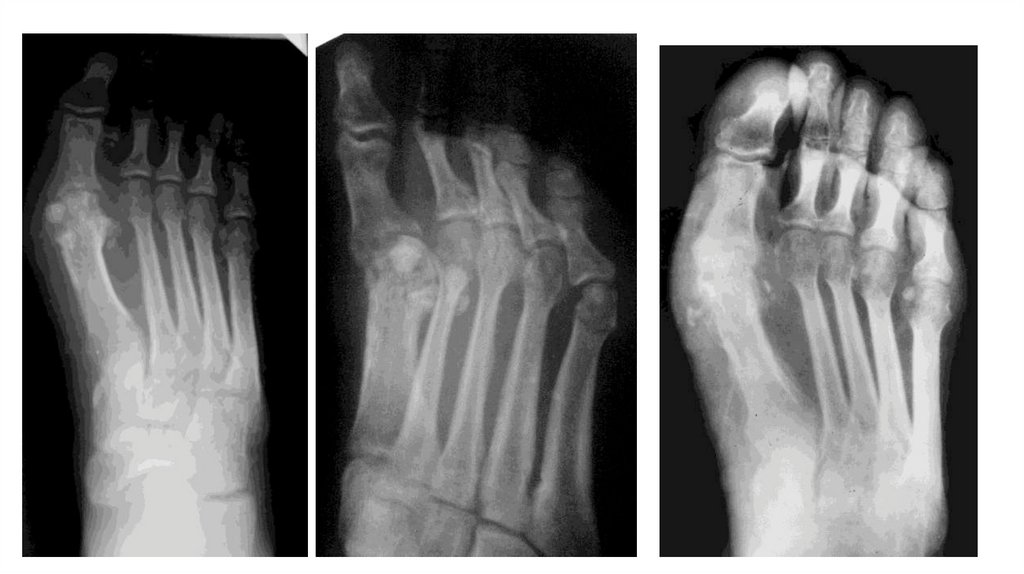

Воспалительные заболевания опорнодвигательного аппарата

«Воспалительные

заболевания опорнодвигательного аппарата»